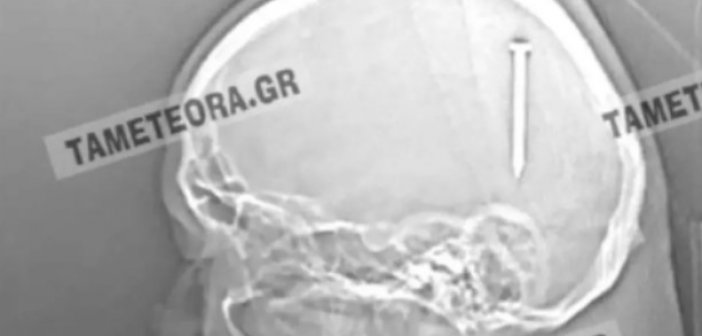

Αν το καρφί βρισκόταν ελάχιστα χιλιοστά από το σημείο που σφηνώθηκε, θα ήταν πολύ επικίνδυνο…

Συνεχίστε την ανάγνωση του άρθρου: Καλαμπάκα: Καρφί 5 εκατοστών σφηνώθηκε στο κεφάλι άνδρα